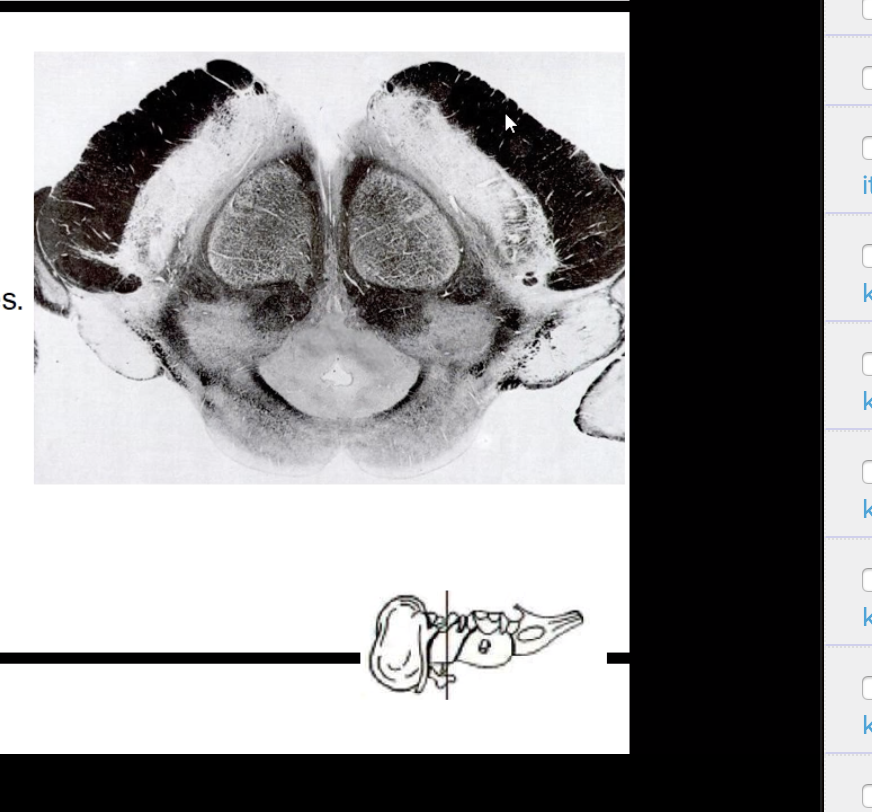

What spinal level is this?

What are some of its characteristics?

Thoracic